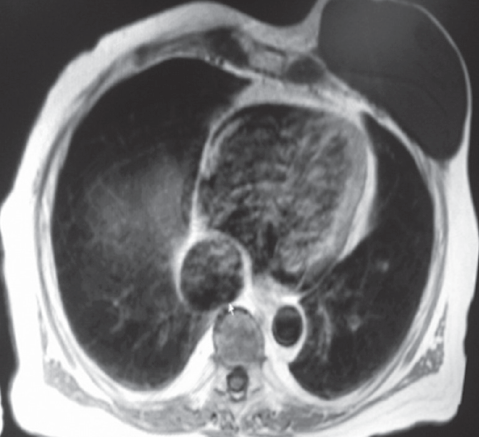

Bisrat Haile, MD; Orlando Carpio, MD; Sameh Abdelaal, MD; Rafael Ilyayev, MD; Rajat Mukherji, MD

A 73-year-old female, nursing home resident, with a past medical history of dementia and breast cancer, was found to have a significant weight loss over a period of 5 months associated with poor appetite. ...